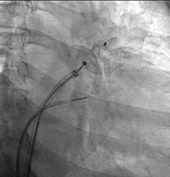

> 即時導引: 借助 ICE 或 TEE 影像以及 X 光透視的雙重即時導引,精準將導管送達並安全穿過心房間隔進入左心房。

> 植入與確認: 釋放選定大小的封堵器,使其穩固展開於左心耳開口。醫師會進行多角度確認,確保位置穩固且沒有殘留滲漏。

依靠心臟內超音波(ICE)的輔助下,病人也可在清楚狀態下以局部麻醉完成手術